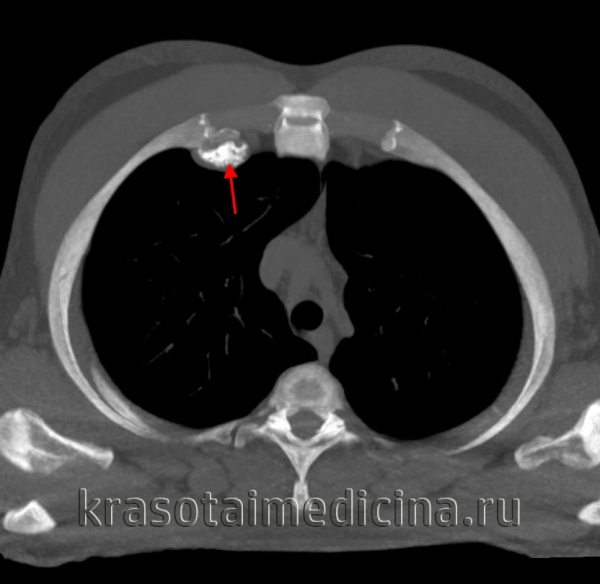

3. КТ при остеохондроме позвоночника:

• Бесконтрастная КТ:

о Костное образование на широком основании или на ножке о Непрерывность кортикального слоя и костномозгового пространства с материнской костью

о Признаки хондроидной кальцификации хрящевого колпачка

о КТ позволяет оценить степень минерализации образования, подтвердить непрерывность его с костномозговыми пространствами позвонка

(Справа) КТ, аксиальная проекция, костный режим: экзостоз тела позвонка, проникающий в спинномозговой канал. Кортикальный слой и костномозговая полость непрерывно связаны с материнским телом позвонка, что характерно для остеохондромы. Обратите внимание на то, что хрящевая крышка не визуализируется. Аксиальное расположение не характерно для солитарных остеохондром, но оно может удивительно часто встречаться у пациентов с множественными наследственными экзостозами. (Слева) Рентгенография в ПЗ проекции: крупное мягкотканное образование над слабозаметной остеохондромой. Экзостоз сложно визуализировать, однако он обладает стандартными характеристиками и развивается из метафиза, с которым связан ножкой, образованной нормальной костью. Растущее новообразование у взрослых должно наводить на мысль о перерождении в хондросаркому.